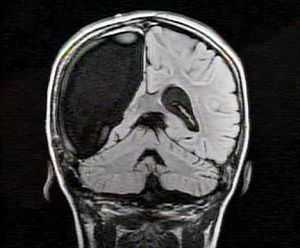

Рис. 6 (а—б). Пример резекции фокальной кортикальной дисплазии I типа лобно-центральной области слева.

Девочка, 5 лет, праворукая, болеющая эпилепсией с 8 мес. На момент операции — очень частые и резистентные к антиэпилептическому лечению эпилептические спазмы и асимметричные тонические приступы, а также начальные признаки задержки в развитии. Учитывая обширность изменений в лобно-центральных отделах доминантного полушария и неопределенность их границ, операцию ограничили частичной резекцией мальформации в пределах премоторной коры при ориентировке в основном по данным магнитоэнцефалографии и интраоперационной электрокортикографии. После непродолжительного и незначительного уменьшения частоты приступов они возобновились и сохранялись вплоть до последнего осмотра спустя 14 месяцев. Исход IVB. а — слева — интериктальная электроэнцефалография, мультирегиональная эпилептиформная активность (нередко — вплоть до гипсаритмии); б — слева — иктальная электроэнцефалография. Тонический приступ с предшествующей ему редукцией и десинхронизацией активности; диффузный разряд пик-волн, совпадающий с началом клинических проявлений, и последующая диффузная низкоамплитудная быстроволновая активность с включением пиков (fast activity). Справа — дооперационные магнитно-резонансные томограммы в режимах T2 и T2-FLAIR, на которых в коре средней и нижней лобных извилин слева отмечается усиление сигнала и нечеткость ее границ с белым веществом, а также линейный участок повышенного сигнала, распространяющийся от левой прецентральной извилины до тела бокового желудочка (стрелка) и симулирующий «трансмантийный тяж», совпадающий с топографией магнитоэнцефалографических источников инициальных разрядов длительных последовательностей, в том числе иктальных (см. также в).

Рис. 6 (в—г). Пример резекции фокальной кортикальной дисплазии I типа лобно-центральной области слева.

в — результаты локализации источников эпилептиформной активности во сне по данным магнитоэнцефалографии. Зелеными точками отмечены источники интериктальных разрядов как одиночных, так и входящих в состав длительных последовательностей, красными — источники начала длительных последовательностей разрядов, на фоне которых у пациентки возникли два тонических приступа. Следует отметить, что эта же зона первой включалась в генерацию многочисленных и длительных интериктальных последовательностей без клинических проявлений; г — слева — вид операционной раны к моменту завершения субпиального опорожнения коры средней и медиальной лобных извилин кпереди от прецентральной борозды (кора нижней лобной извилины сохранена с учетом доминантности полушария); справа — иммуногистохимический препарат — видны выраженные нарушения корковой архитектоники по смешанному типу (экспрессия NeuN, ×100).